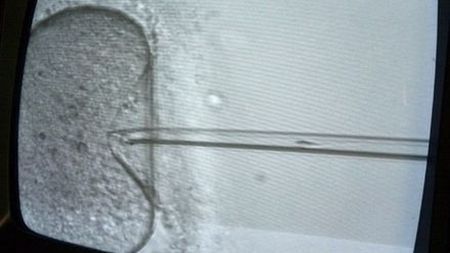

Obraz

Źródło zdjęć: © AFP